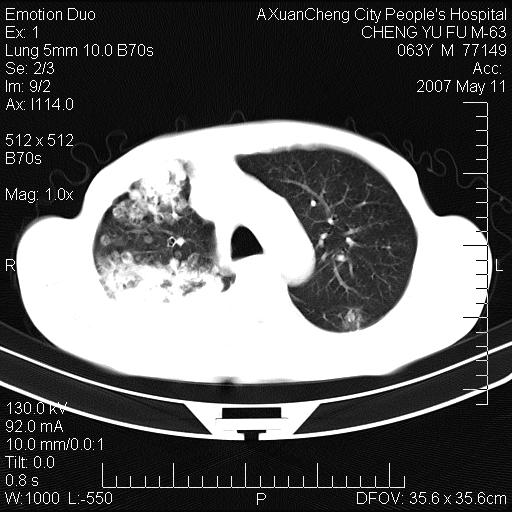

以下是引用小初学者在2007-5-11 19:32:00的发言:[br]1、首先考虑干酪性肺炎支气管播散[br]2、支气管肺泡癌待排

以下是引用zhangzhongshou在2007-5-11 19:30:00的发言:[br]细支气管肺泡癌可能性大。